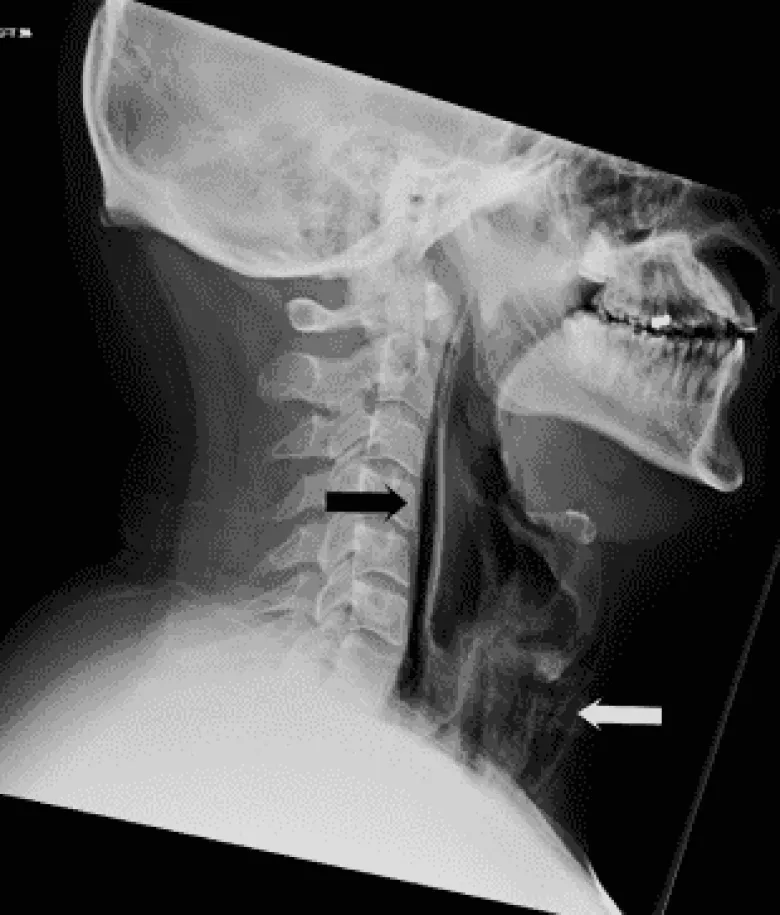

Այս արտասովոր դեպքը նկարագրվել է BMJ Case Reports ամսագրում: Պարզվել է, որ տղամարդը փռշտալու պահին փակել է բերանը և քիթը, ինչի հետևանքով նրա ըմպանի ստորին հատվածը՝ կերակրափողի հետ միացման մասում, պատռվել է, իսկ կոկորդը՝ այտուցվել:

Նշվում է, որ հետազոտության ժամանակ ճտճտոց է լսվել, երբ բժիշկները սեղմել են տղամարդու վիզը և կրծքավանդակը:

Աղբյուրը մանրամասնում է, որ կրեպիտացիա կոչվող այս ախտանշանն առաջանում է, երբ մաշկի տակ օդ է մտնում: Դրանից բացի, համակարգչային տոմոգրաֆիայի միջոցով պնևմոմեդիաստինում է ախտորոշվել. սա օդի կուտակումն է միջնորմի հյուսվածքներում: